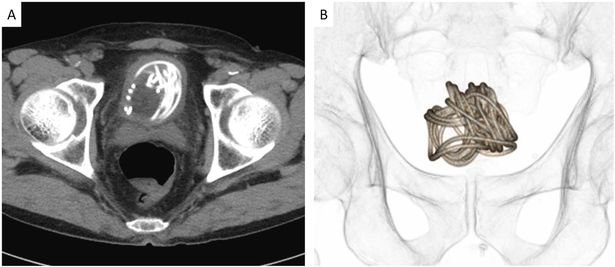

İpin ince olduğuna dikkat çeken doktorlar, ipin düğüm olması sebebiyle idrar torbasına bir delik açarak cerrahi bir müdahale gerçekleştirildiğini de duyurdu. Ameliyatın başarılı geçmesi için idrar torbasının 3-D modelinin yapıldığı ve bu sayede doktorların nasıl müdahale edeceklerinin anlaşıldığı açıklandı.

Tokyo'nun 160 kilometre uzağında yaşanan olay Urology Case Reports isimli tıp dergisinde yayınlandı. Araştırmayı kaleme alan ve operasyonda da yer alan Profesör Toshiki Kijima, "Tarama ve modelleme teknolojisi ameliyatın başarılı geçmesine katkı sağladı" dedi.